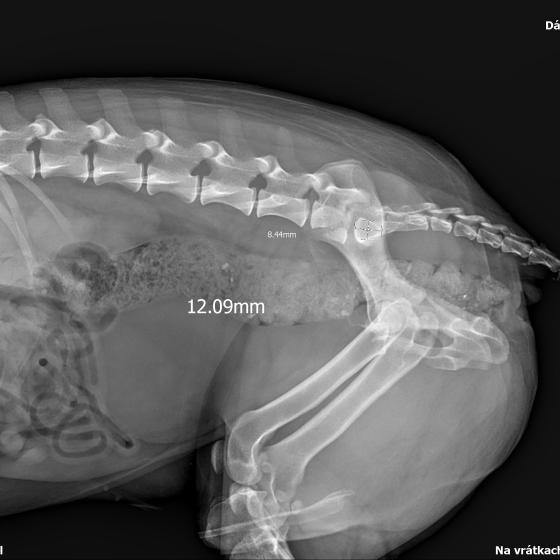

Karola nám doviezla pani, ktorá ho našla, asi jediná dobrá duša, ktorá pri ňom neprešla so zatvorenými očami. Ihneď sme s krpcom utekali na veterinu aby sa zistila závažnosť jeho zranení. Hneď pri prvých RTG snímkoch sa ukázala obojstranná fraktúra panvy, taktiež fraktúra krídla panvy a keby mu to chudákovi nestačilo, do tretice sa objavila zlomenina stavca. Karolko mal neznesiteľné bolesti, ale krásne prečkal vyšetrenie lebo vedel, že je v dobrých rukách a dostáva sa mu pomoci. Po nálezoch sme okamžite kontaktovali neurológiu a ortopédiu na veterinárnej klinike Sibra - centrum veterinárnej medicíny, kde sme dostali hneď termín na príjem.

Karol nemá žiadne neurologické deficity, po ortopedickej operácii bude vedieť behať a bez problémov bude vedieť samostatne cikať a kakať. Po tejto úžasnej správe sme samozrejme dali zelenú náročnej ortopedickej operácii pod vedením MVDr. Vatolíka. Operácia sa podarila na výbornú, Karči je "zoskrutkovaný" a vôbec nič mu nebráni v tom, aby opäť mohol behať a aktívne žiť. Momentálne sa zotavuje po operácii, musí mať prísny kľudový režim. Po vybratí stehov ho čaká hydro- a fyzioterapia, ktorá mu pomôže postaviť sa na nohy. Je to bojovník, veľmi sa chce uzdraviť a v jeho očkách je dokonale vidieť, že už kuje plány čo všetko zameškané bude musieť dobehnúť.